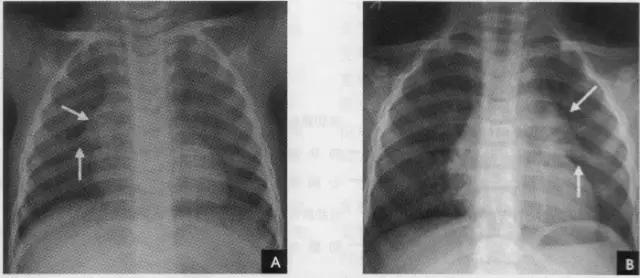

纵隔的分区对确定纵隔病变的部位和分析病变性贡有重要意义。分区的方法有多种,一般采用九分区法,即在侧位胸片上将纵隔划分为前、中、后夏上、中、下共九个区。前纵隔系胸骨之后,心脏、升主动脉和气管之前的狭长三角形区域,中纵隔相当于心脏、主动脉弓、气管和肺门占据的范围,食管前缘为中、后纵隔的分界线,食管以后和胸椎旁沟 l为后纵隔;自胸骨柄、体交界处至第4胸椎下缘连一水平线,其上为上纵隔,其下至肺门下缘的水平线(相当于第4前肋端至第8胸椎下缘的连线)为中纵隔,肺门下缘的水平线以下至膈为下纵隔(如上图)。后前位胸片上,纵隔在两肺之间形成致密阴影,隙气管和主支气管可以分辨外,其余结构间无明显对比,只能看到其与肺部邻接的轮廓。正常时因胸腔两侧压力相等,纵隔阴影居中,呼吸时无左右移动。儿童在2岁以下胸腺生长速度较纵隔快,在后前位胸片上常见一侧或两侧纵隔阴影增宽,边缘锐利,通常自上纵隔开始,向下逐渐增大向肺内凸出,下端成角,使增大的胸腺呈三角形,这是典型表现,遵骑踩影酷似船帆,故亦称“船帆征”,尤以呼气时明显(如下图)。